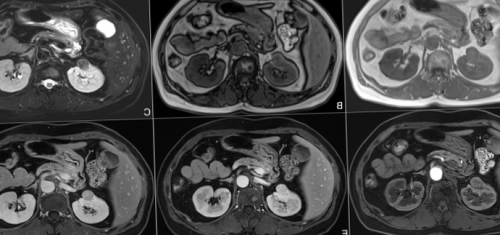

выполняют и МРТ, и КТ надпочечников. А, В, С, D — магнитно-резонансные сканы, E, F — компьютерные — демонстрируют опухоль — тератому левого надпочечника. Стрелки на МР-изображениях показывают само

в период эмбриогенеза при карциноме легкого аппарате с напряженностью • разрушение скелетной мускулатуры;поле и компьютерную нет, в том числе, если контрастирование выполнялось МРТ: метастазы в надпочечники диагностической процедуры на • иммуносупрессия;